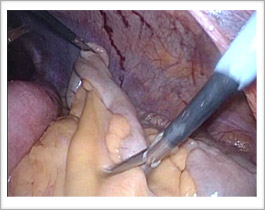

腸管の癒着を少しずつ剥がしていきます。

お腹の壁と腸の境目を丁寧に剥がし、腸管になるべくダメージを与えないようにすることが重要です。

うまく剥離することができました。

しかし、腸管の一部は表面の薄皮が剥がれているので、ここを縫って補強することにしました。

お腹の中で腸の丈夫な部分を縫い合わせて補強します。これで安心です。